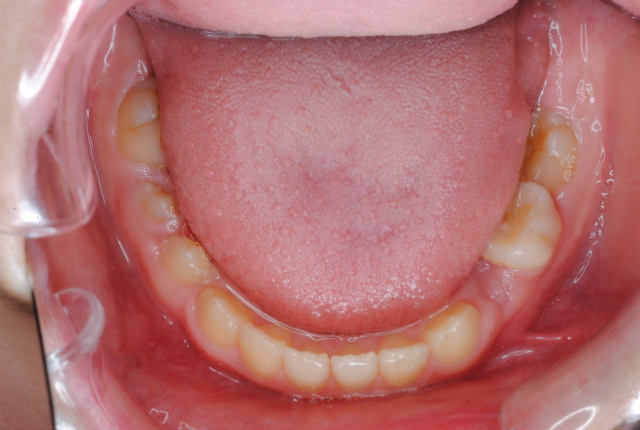

下の写真のように一見歯並びがきれいに並んでいて問題がないように見えますが、舌で前歯を常に押しているから歯並びが整っているに過ぎません。下顎歯列上に舌が覆いかぶさってしまっている様子がおわかりでしょうか。

現在 舌挙上のトレーニング中